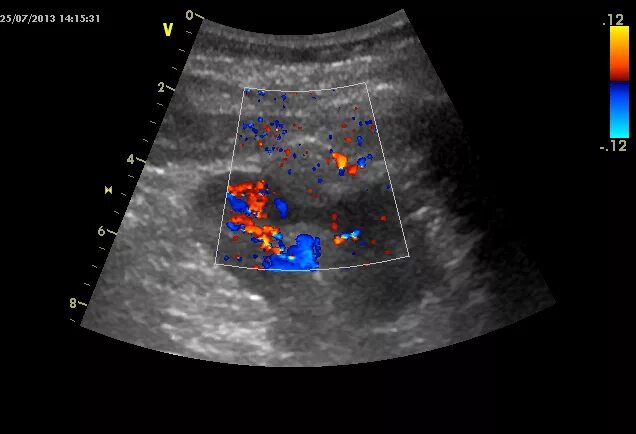

Нефросклероз почек на узи что это такое